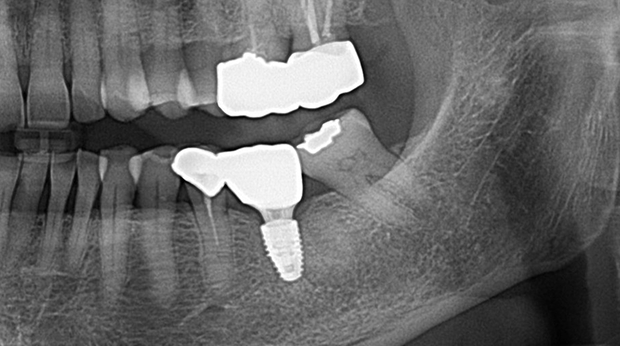

임플란트와 사랑니 발치는 외과적 시술로 잇몸을 절개하는 외과적 시술은

짧으면 짧을 수록 시술 후 붓기와 통증이 최소화됩니다.

치과의사 경력 14년차 구강외과 전문의가 빠르고 안전하게, 아프지 않게 수술해 드립니다.

치과경력 14년차 구강외과 전문의